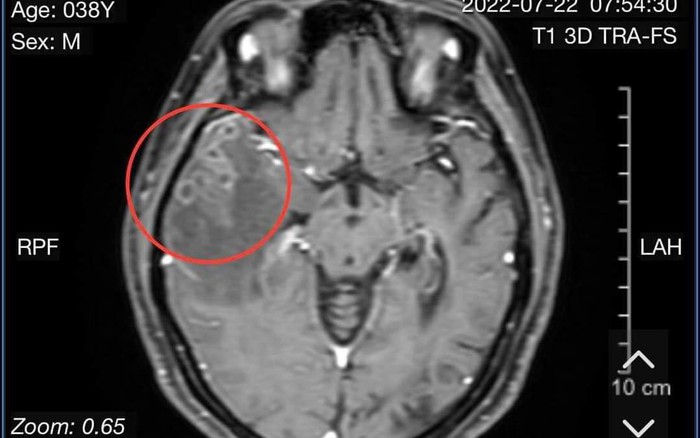

Hình ảnh phim chụp của bệnh nhân

Bệnh nhân nhập viện với triệu chứng đau đầu dữ dội và có nhiều cơn co giật. Tại BV, hình ảnh chụp cổng hưởng từ sọ não có tiêm chất tương phản cho thấy người bệnh bị tổn thương não do sán.

Tại BV, hình ảnh chụp cổng hưởng từ sọ não có tiêm chất tương phản cho thấy người bệnh bị tổn thương não do sán. Kết quả xét nghiệm giải phẫu mô não có nhiều ổ viêm hạt, trung tâm chất hoại tử bao quanh lympho, đại bào nhiều nhân, tương bào và tế bào sợi.

Kết luận của bác sĩ về bệnh tình của người bệnh là tổn thương viêm não do nang sán. Sau khi hội chẩn, BV chỉ định phẫu thuật để xử lý ổ sán.